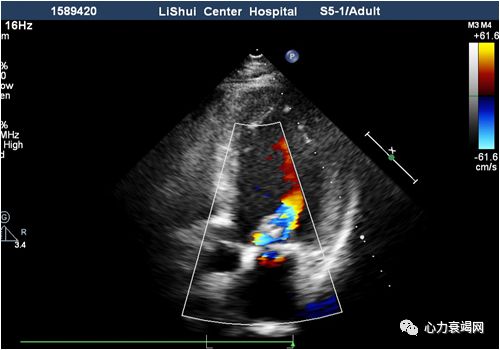

➤ 全心扩大(左房内径41mm,左室内径(d)70mm,(s)58mm)

➤ LVEF36%,肺动脉血流未见异常

➤ 二尖瓣收缩期见轻微返流

➤ 室间隔厚09mm,左室后壁厚10mm

为什么心力衰竭症状再发?

为什么心脏再次扩大?

自行停服任何药物1年

吸烟

饮酒

肺部感染

心肌病?